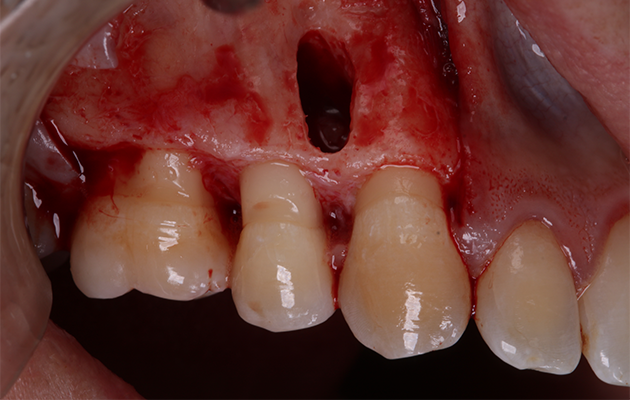

6 e 7 | Descolamento vestibular e janela de acesso à lesão.